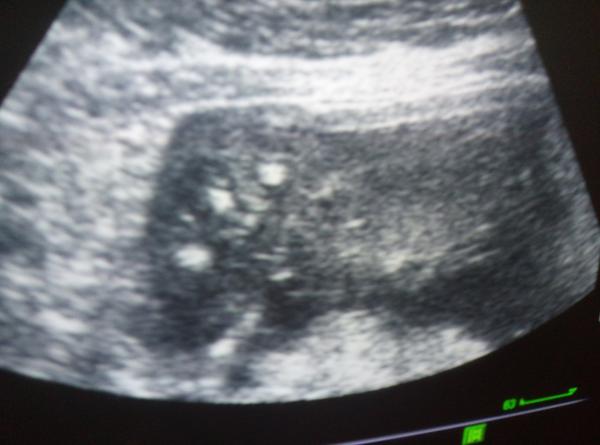

Ultrazvuk v 19. týdnu těhotenství. Jde poznat pohlaví?

Holky, chtela jsem se zeptat, zda jste mela nektera ultrazvuk v 19tt a jestli uz jde poznat pohlavi. Je to velky rozdil mit ultrazvuk v 19 nebo 20 tydnu?

Aha tak super, no ono mi nejde samozrejme jen o zjisteni pohlavi ale i o to zda je mimi ok, zdrave atd. Tak to se taky uz v 19tt pozna ne? Stejne jako od 20tydne nebo ne?Kazdopadne se uz nemuzu dockat🙂

Odkdy se dela v CR ten geneticky velky ultrazvuk? Taky od 19 tydne ne?Pry je jedno jestli ve 20 nebo v 19tydnu.